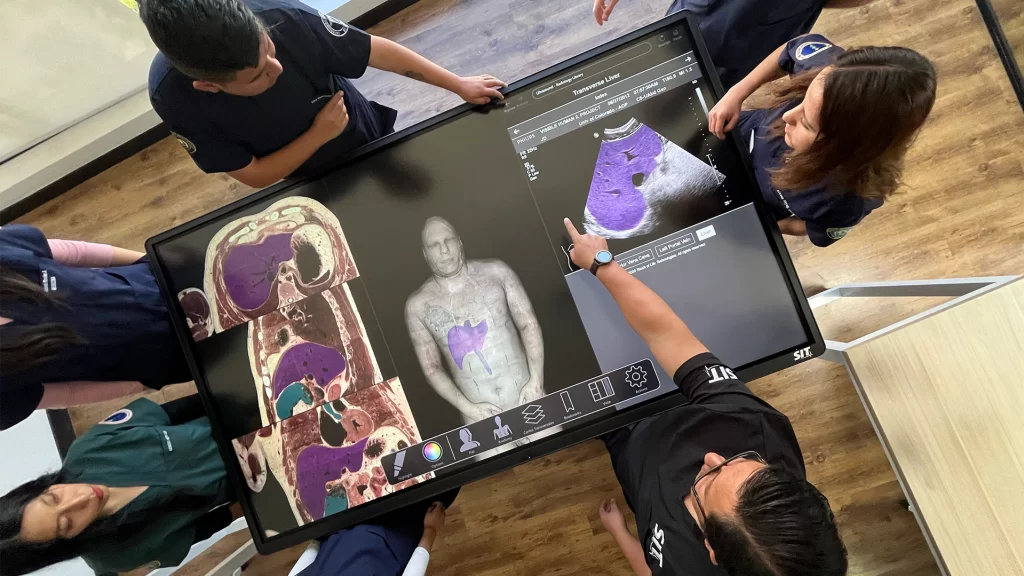

SIT Anatomy

La mesa SIT Anatomy es una solución versátil de alta tecnología con modelos 3D basados en cadáveres reales y renderizados foto realísticamente. Ofrece:

Exploración detallada de la anatomía humana y veterinaria

Herramientas interactivas de disección virtual

Visualización de imágenes DICOM y PACS

Estudio morfofuncional con correlación clínica

Ideal para facultades de Medicina, Enfermería, Fisioterapia, Veterinaria y Odontología.